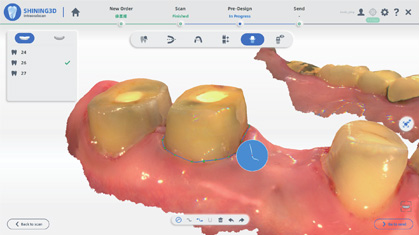

智能掃描

掃描更流暢

軟件智能識別并擯除頰舌側等雜余數據,實時數據干凈清晰無 干擾,口掃更加快速準確。

正畸模擬

效果預覽 完美預定

智能識別自動分牙、排牙

口掃數據直接輸出正畸模擬

生成二維碼分享

口掃數據直接輸出正畸模擬

生成二維碼分享

口掃打印一體化

集成AccuDesign模型編輯工具,支持快速封底、抽殼、加字、排溢孔、智能添加頜架等操作。

支持在椅旁直接打印患者口內數據,輔助醫患達成良好的診療溝通。

支持在椅旁直接打印患者口內數據,輔助醫患達成良好的診療溝通。

廣泛應用 如魚得水

Aoralscan3口內掃描儀,適應癥覆蓋種植、修復、正畸三大領域。無論是椅旁即刻解決方案,還是“診所+技工”聯動解決方案,Aoralscan3都將給您流暢的使用體驗。